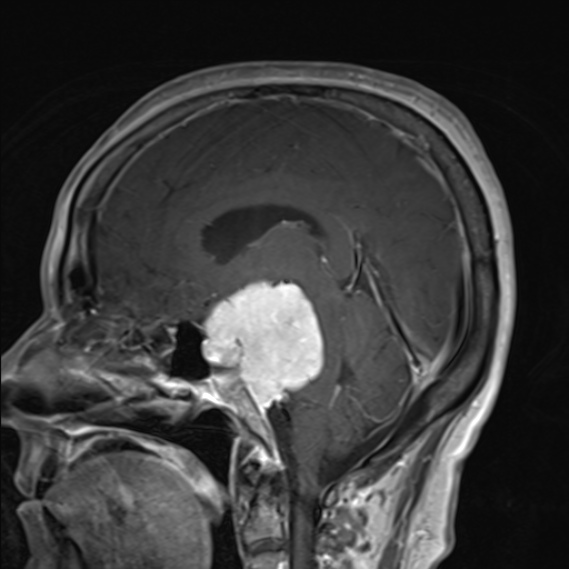

面神经麻痹和三叉神经感觉减退均有轻微好转。图示:(A)32岁女性,左侧颈面部运动障碍,轴向T2加权SEMR图像显示左侧岩斜坡脑膜瘤压迫脑干。图示:(A)32岁女性,左侧颈面部运动障碍,...

岩斜脑膜瘤(PCMs)由于其与脑干、主要血管结构、穿支和颅神经的关系,一直是颅底外科医生面临的挑战。手术入路的选择取决于肿瘤的位置、范围、大小、患者年龄、术前听力和面神...